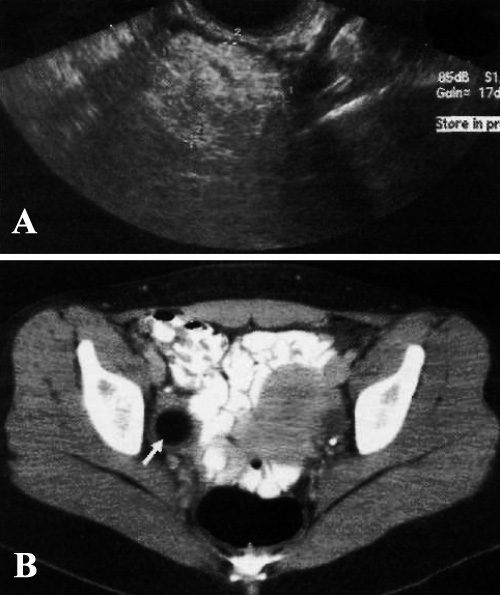

Ультразвуковые признаки ВЗОМТ имеют довольно широкий спектр – от эндометрита, характеризующегося утолщением эндометрия и скоплением жидкости в полости эндометрия (фото 5), до тубоовариального абсцесса (в том числе пиосальпинкс, гидросальпинкс, скопление жидкости в Дугласовом пространстве).

Фото 5. Эндометрит. Продольная сонограмма матки демонстрирует утолщенный, неоднородный, гипоэхогенный эндометрий (фото А – стрелка; фото В – курсор)

Бывают случаи, когда жидкость в Дугласовом пространстве визуализируется на УЗИ как плотная масса с разнородной эхоструктурой, которая окружает органы таза.